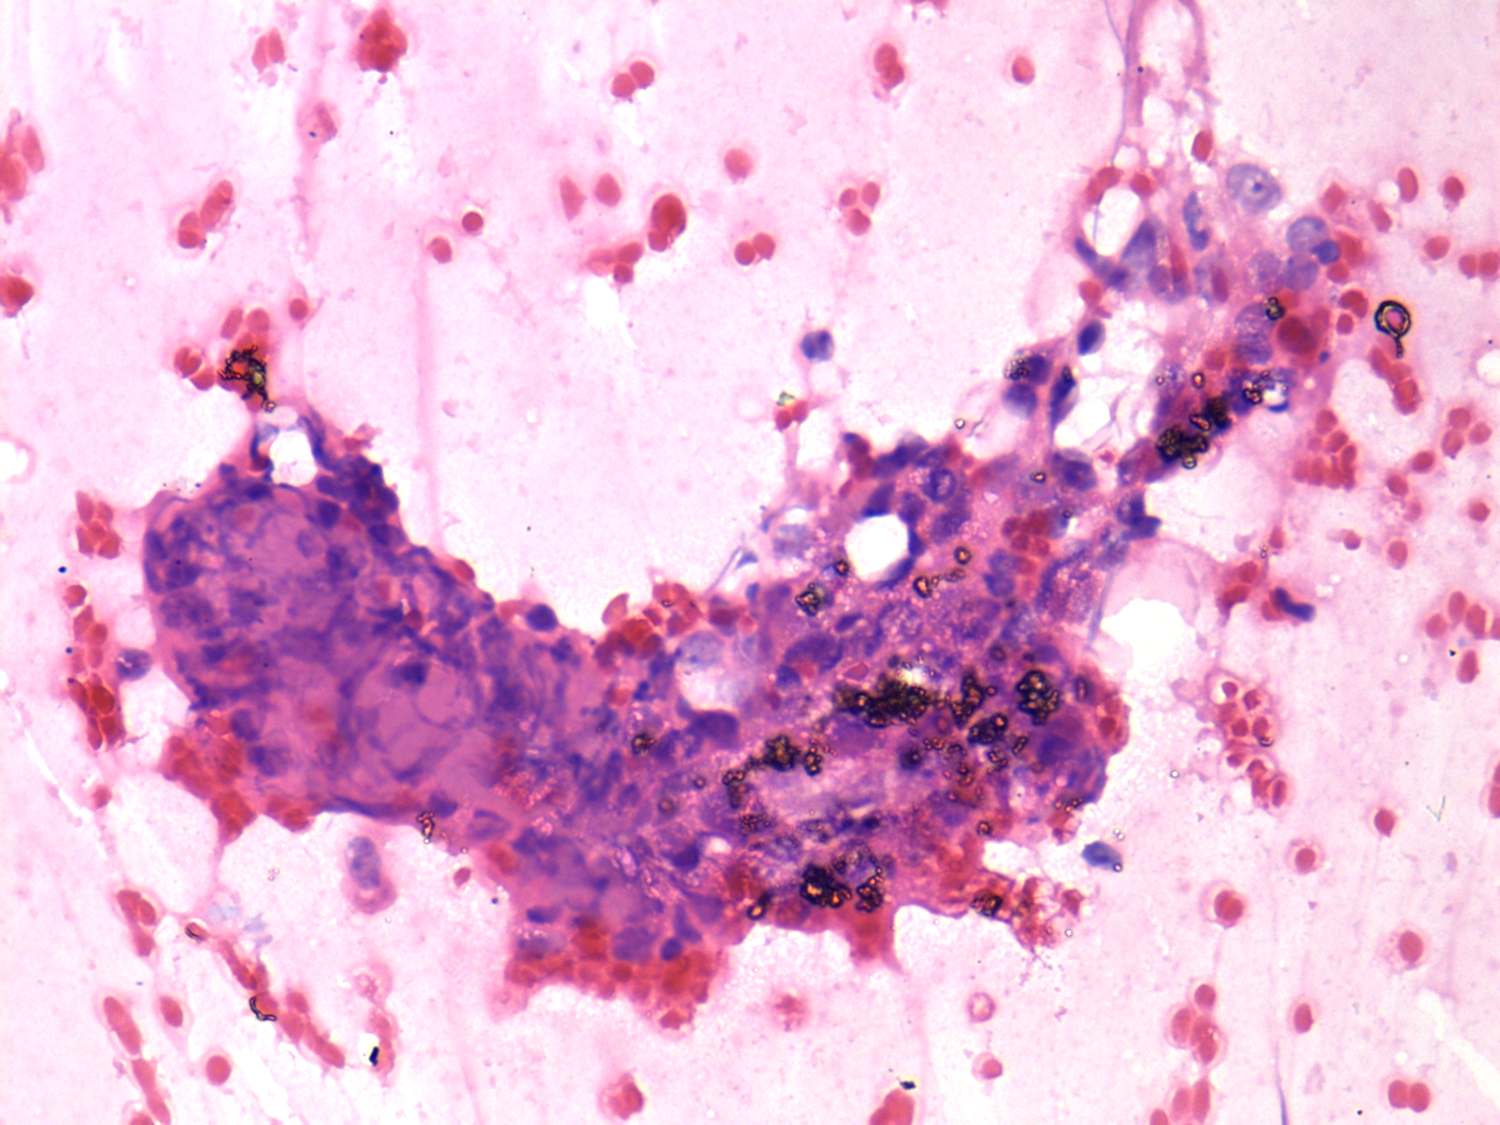

De Quervain's thyroiditis - Figure 4. Cytological presentation. The pathognomic sign of a de Quervain's thyroiditis would be a granulation tissue. Because of the size of this structure, we cannot aspirate in toto and therefore only part of the granulation tissue can be seen in cytology. In certain cases we can recognize this in cytological smears. |